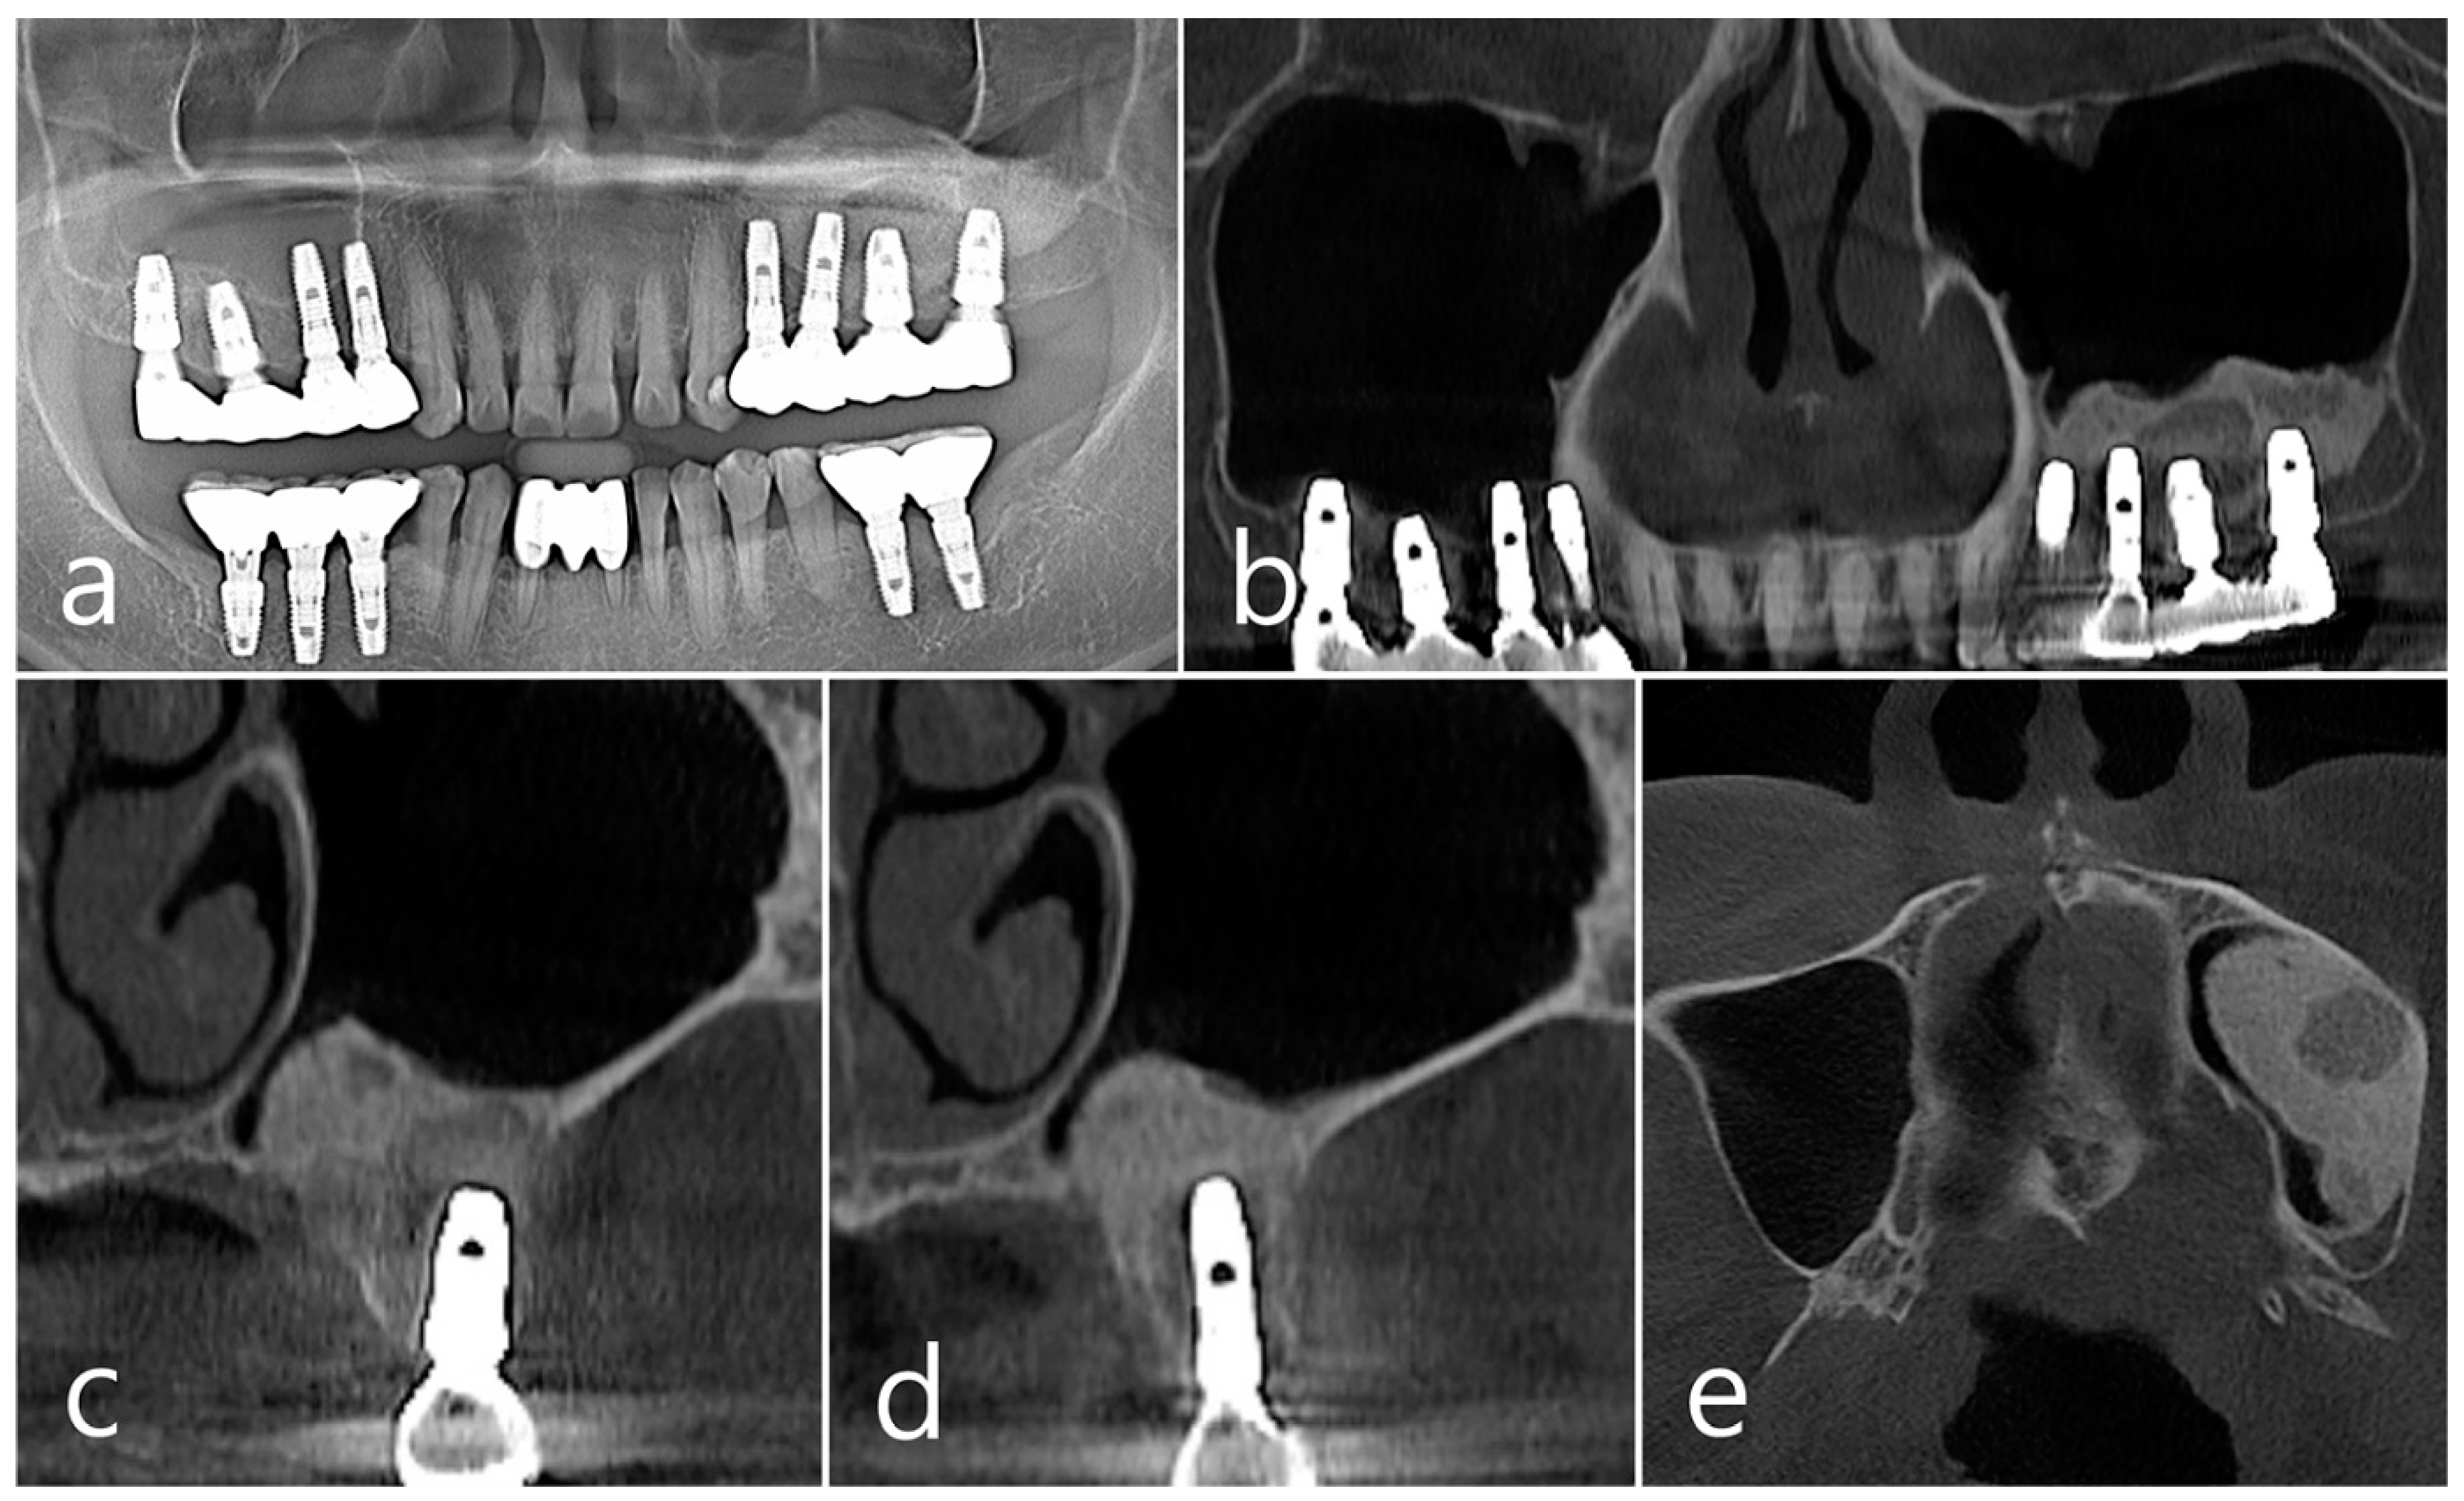

2.2. Case 2

This patient was a 58-year-old male smoker who was taking antihypertensive drugs. The patient visited our clinic for implant placement in the upper left posterior region. Teeth #24 and #25 were determined to be extracted due to severe periodontal disease. In panoramic radiography, the residual alveolar bone was severely atrophied, and pneumatization of the maxillary sinus was severe (Figure 7a). In CBCT imaging, membrane thickening was observed in the sinus floor, but there was no membrane thickening in the rest of the sinus wall (Figure 7b–d).

Under local anesthesia, teeth #24 and #25 were extracted, midcrestal and vertical incisions were performed, and mucoperiosteal flaps were reflected (Figure 8a). A lateral sinus window was prepared in the buccal sinus wall, and sinus floor elevation was performed without membrane perforation. As a bone graft substitute, 1 cc of Osteon II (Genoss, Suwon, Republic of Korea) hydrated with saline solution was used (Figure 8b), and a resorbable collagen membrane (Genoss, Suwon, Republic of Korea) was covered (Figure 8c). The flap was closed using 4-0 nylon. Healing was uneventful, and there were no clinical symptoms until 6 months after surgery.

In the CBCT image taken immediately after the procedure, a well-filled bone graft substitute without perforation of the sinus membrane was observed (Figure 8d–f). However, extensive bone loss was found in CBCT images taken 2 years after the prosthesis was placed. The facial cortical bone plate was lost, and bone resorption was present only within the sinus graft. The appearance of the sinus graft was not invaded, and the thickness of the sinus mucosa was normal (Figure 8g–i).

Figure 7. Case 2. (a,b) On the preoperative panoramic radiography and panoramic image of CBCT, the residual alveolar ridge in the posterior maxilla was severely atrophied and pneumatization of maxillary sinus was severe; (c,d) In CBCT imaging, mucosal thickening (arrows) ranging from 2 to 15 mm was observed in the sinus floor, depending on the location, but there was no mucosal thickening in the rest of the sinus wall.

Figure 8. (a) Teeth #24 and #25 were extracted, midcrestal and vertical incisions were performed, and mucoperiosteal flaps were reflected; (b,c) A lateral sinus window was prepared, and sinus floor elevation was performed without membrane perforation. The bone graft substitute was delivered and covered with a resorbable collagen membrane. The flap was closed; (df) In the CBCT image taken immediately after the procedure, a well-filled bone graft substitute without displacement was observed; (gi) Extensive bone resorption around #26 implant was observed in CBCT images taken 2 years after prosthesis delivery. The buccal cortical bone plate was lost, and bone resorption was present only within the sinus graft.